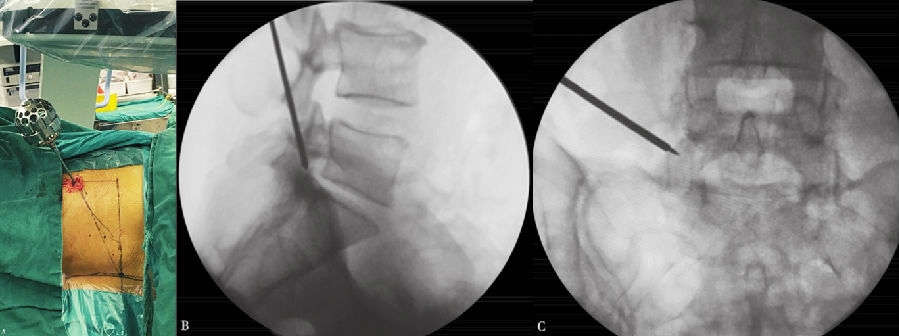

4. 穿刺

以L5~S1为例,根据髂嵴的高低,针尾向头侧倾斜约 40°~60°,外展角约 30°~50°,定位针在正位X线透视下刚好位于后背正中的棘突连线上,侧位X线透视下则紧贴上关节突腹侧,下缘位于下位椎体的后上缘。(图6)

做大约1cm皮肤切口,用导丝置换穿刺针,沿导丝用扩张器逐级扩大软组织。(图7、图8)

6. 置入定位器

在上关节突上打孔,退出扩张器,再磨除部分关节突关节,逐级扩大椎间孔。(图9~图13)

图5-图9 A:使用利多卡因进行局部分层麻醉(皮肤、皮下组织、筋膜、关节突周围);B:穿刺针X线片侧位投影图;C:穿刺到位后交换导丝;D:导丝引导下通过导杆、三级套管扩张肌肉及软组织;E:导丝引导下交换Tom针,定位上关节突

图10 Tom针定位上关节突

A. Tom 针定位上关节突;B.Tom 针X 线片侧位投影图;C.Tom 针X线片前后位投影图

图11-图13 6mm扩孔骨钻扩孔过程中;6mm扩孔骨钻侧位X线片投影图;8mm扩孔骨钻前后位X线片投影图